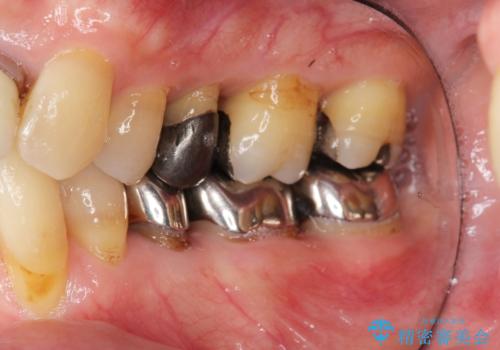

- 前歯の見た目・歯並び・銀歯の見た目の改善を求めて来院されました。

まずガタ付きの強い歯並びをマウスピース矯正インビザラインで整えたのち、セラミック治療による審美性の改善を計画します。

矯正治療が終わったのちに、精度の高いセラミックを装着することでより安定した噛み合わせとなり審美性も兼ね備えた口腔内状態で治療を終了し、今後のメンテナンスを行っていくことができます。